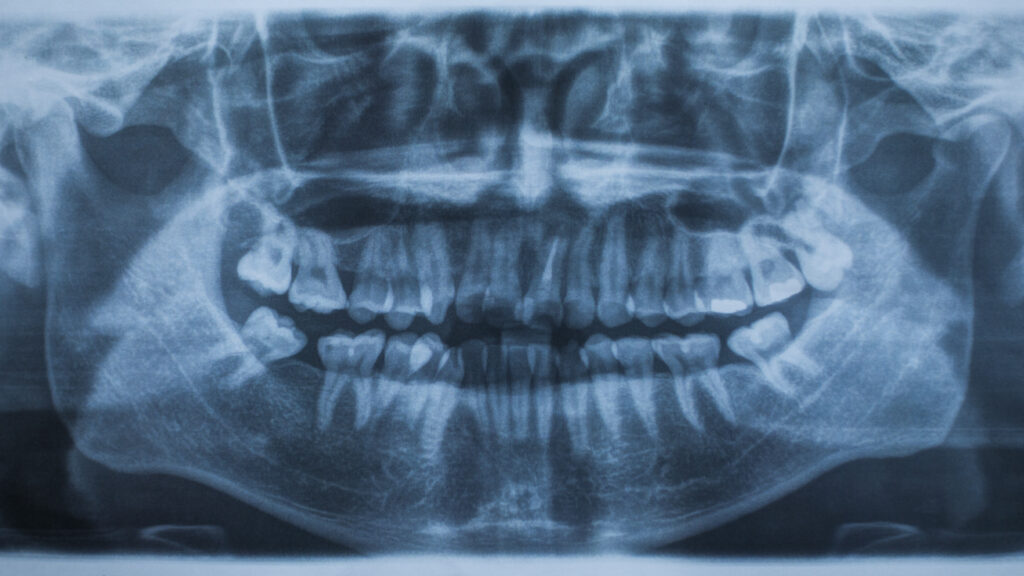

The first step in any orthodontic treatment is a thorough consultation, which includes X-rays and dental molds to plan the appropriate treatment. At Clínicas La Guardia, we use cutting-edge technology to ensure an accurate diagnosis and a personalized treatment plan that meets the specific needs of each patient.

Advanced Radiological Diagnosis

Advanced radiological diagnosis is a fundamental tool in modern dentistry. Using 3D technology, this method provides a detailed and accurate view of oral health, which is essential for planning and executing complex treatments such as dental implants and maxillofacial surgery.

- Provides accurate and detailed images of the dental structure: 3D technology allows for high-resolution images of teeth, bones, and surrounding tissues. This provides a complete understanding of dental anatomy, crucial for an accurate diagnosis.

- Improves treatment planning and execution: With a clear and precise view, dentists can plan treatments more accurately. This is particularly important in procedures such as implantology and orthodontics, where precision is key to success.

- Reduces the risk of complications during procedures: By having a detailed image of the oral structure, dentists can anticipate and avoid potential complications. This results in safer and more effective procedures, with a faster recovery for the patient.

- Dental Implants: Implant planning requires a detailed assessment of the jawbone and surrounding dental structure. 3D images ensure precise and safe implant placement.

- Maxillofacial Surgery: Complex surgical interventions in the jaw and face benefit greatly from 3D images, which allow meticulous planning and precise execution.

- Orthodontics: In orthodontic treatments, 3D images provide a clear view of dental alignment and bone structure, facilitating a personalized and effective treatment plan.